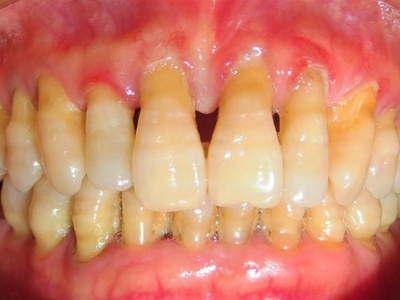

牙龈退缩露出淡黄色牙根图

牙龈退缩患者的牙龈退缩后,淡黄色牙龈明显露出。若进一步发展,易使对应位点的牙槽骨发生骨吸收,可能诱发龋齿、牙龈敏感、菌斑堆积等。